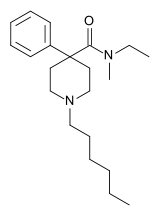

4-Phenylpiperidines

Pethidines (meperidines)

Structures